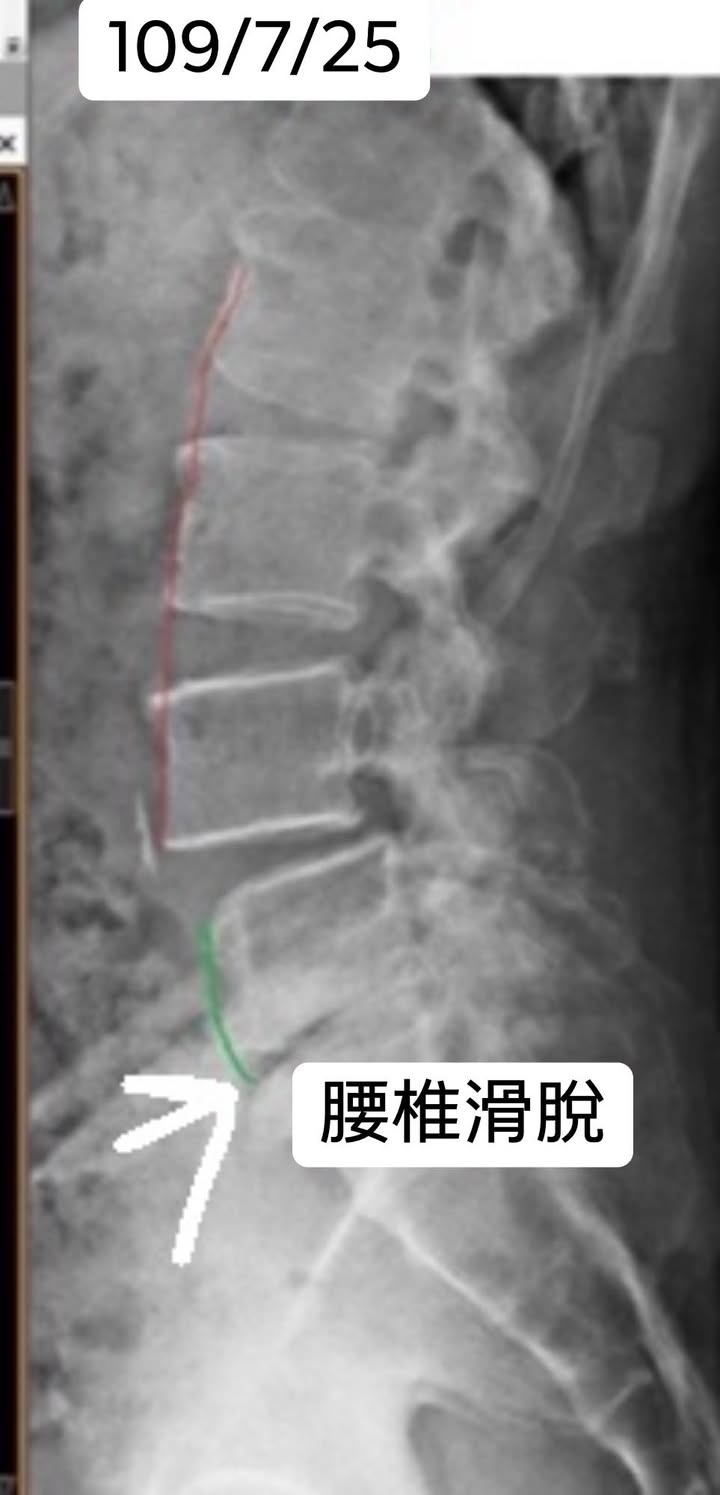

Cervical Spine Treatment Cases 腰椎治療案例 #腰椎手術失敗綜合症候群 #術後沒保養還是又繼續椎間盤突出 #感謝台北梁小姐熱情見證 ... 2021.03.02 #超感動醫案感謝中壢姚阿姨見證 #原本已經坐輪椅的人生看到一絲希望 #脊刻救援牛轉乾... 2021.02.22 #感謝新北中和區陳大哥熱情見證 #從北到南看過眾多中西醫民俗療法 #腰痛到連躺跟坐都... 2021.02.17 #感謝桃園龜山蘆先生熱情見證 #腰椎跟屁股痠痛超過十二年 #腰椎纖維環裂隙導致神經根... 2021.02.16 #騎馬摔傷腰椎醫案 #感謝內湖陳先生熱情見證 #椎間盤突出合併輕微椎間孔狹窄 #重新騎... 2021.02.03 #巨大椎間盤突出醫案 #脊椎整合中醫微創逆轉勝 #感謝三峽林先生熱情見證 #為何突出的... 2021.01.29 #腰椎粉碎性骨折手術後調養醫案 #坐輪椅的人生終於看到希望 #脊椎手術失敗症候群 #Fai... 2021.01.26 #感謝台中市大肚區患者熱情見證 #第二次治療腰痛好超多 #腰酸痛時間快一年了 #親筆寫... 2020.12.05 #腰椎嚴重滑脫醫案 #原本左腳麻痛無法久站超過十分鐘 #脊椎整合中醫微創療法逆轉勝 #... 2020.12.02 #感謝林口楊先生熱情見證 #椎間盤整和中西醫微創療法逆轉勝 #曾經大痛到無法走路嚴重... 2020.11.25 #今天來聊巨大骨刺為何可以吸收回去! #椎間盤突出需要多久才能吸收呢? #馬尾神經症候... 2020.11.10 #腰椎滑脫一定要開刀嗎? #骨科認為開刀置放骨釘穩定錐體 #如果患者可以藉由增強肌... 2020.11.04 #六年的長期腰酸痛醫案 #原來是椎管狹窄合併輕微突出 #每年冬天準時發作苦不堪言 #感... 2020.10.31 #椎管狹窄案例 #感謝新莊陳大哥熱情見證 #腰酸痛數年原來是椎管狹窄 #來診前已經痛到... 2020.10.28 #知名四代魚丸店掌門人熱情見證 #腰椎中醫微創逆轉勝 #椎間盤突出醫案 #感謝新北... 2020.10.23 ← 上一頁 8 9 10 11 12 下一頁 →